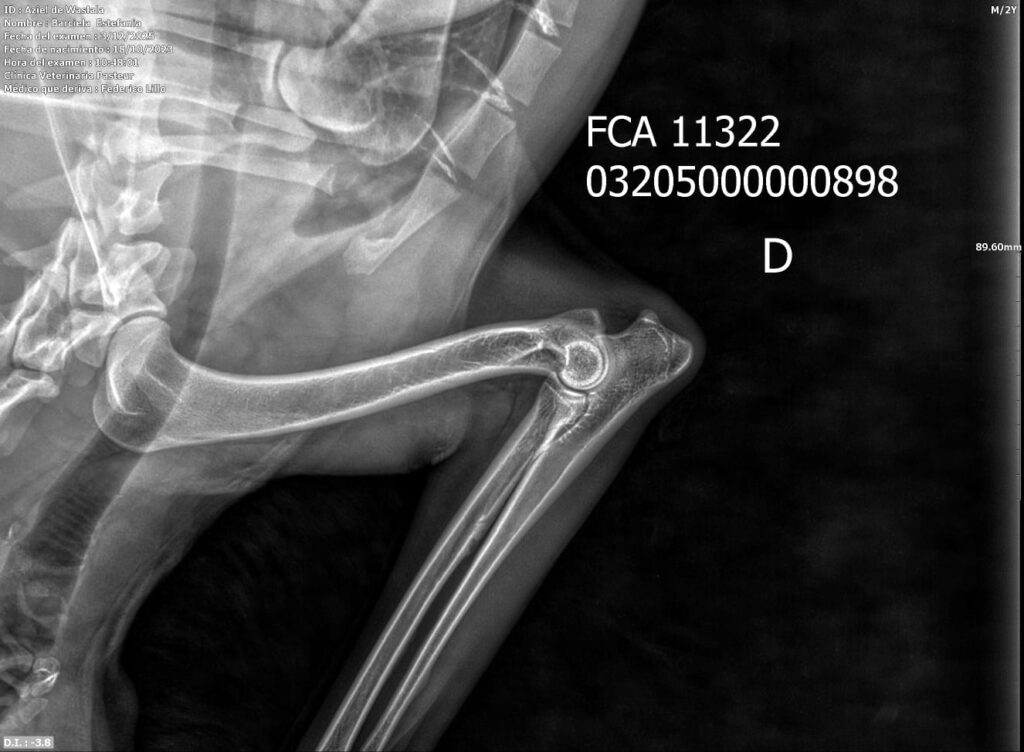

Placas de caderas y codos en La Rienda Border Collie

Realizamos radiografías oficiales de caderas y codos a nuestros reproductores, evaluadas por profesionales veterinarios especializados.

Estos estudios permiten detectar posibles patologías hereditarias, como la displasia de cadera y de codo, ayudando a reducir su incidencia generación tras generación.

✔ Clasificación A en caderas y codos, indicativo de articulaciones sanas y excelente conformación

✔ Clasificación A en codos y B en caderas, siempre informada con total transparencia y criterio de selección responsable